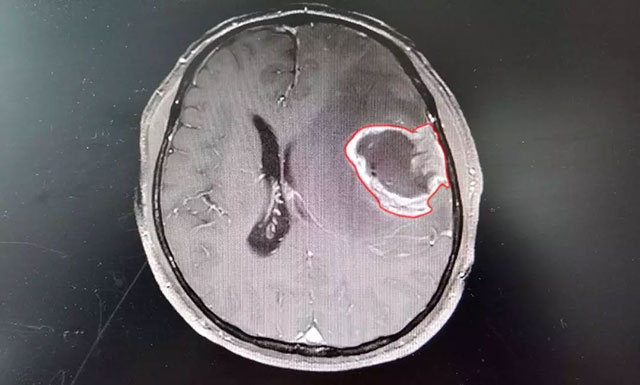

在蓝十字脑科医院,头颅磁共振增强扫描影像进一步明确:钱先生左额颞叶占位性病变,类椭圆形团块状异常信号大小约4.3*3.2cm,边界不清,病灶周围有明显水肿。从症状体征和影像学资料判断,钱先生患上脑胶质瘤的可能性很大,通过对患者术后病理标本检验,也印证了该结论。

▲ 患者术前磁共振增强扫描影像